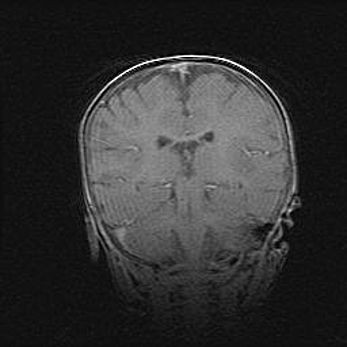

Множественные кисты обоих полушарий головного мозга, наибольшая из них в правой затылочной области. Ассиметричная атрофическая гидроцефалия.

Возраст: 7 месяцев

Вес: 5660 г

Пол: мужской

Окружность головы: 41,5 см

Срок гестации: 28-29 недель

Кисты головного мозга развиваются в результате многоочаговых некрозов вещества мозга и возникают вследствие перенесенной перинатальной инфекции, менингитов, энцефалитов, асфиксии, родовой травмы, расстройств мозгового кровообращения различного генеза. Образованию кист в веществе головного мозга плодов и новорожденных способствуют такие факторы, как высокое содержание в нем воды, недостаточная (или отсутствие) миелинизация и слабая астроглиальная реакция на повреждение.

Кисты могут сочетаться с гидроцефалией и другими поражениями головного мозга.